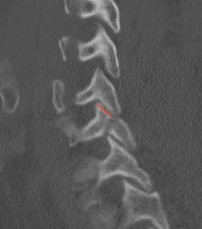

< 40% of the lateral mass

Superior articular facet fracture approximately 50% of the lateral mass